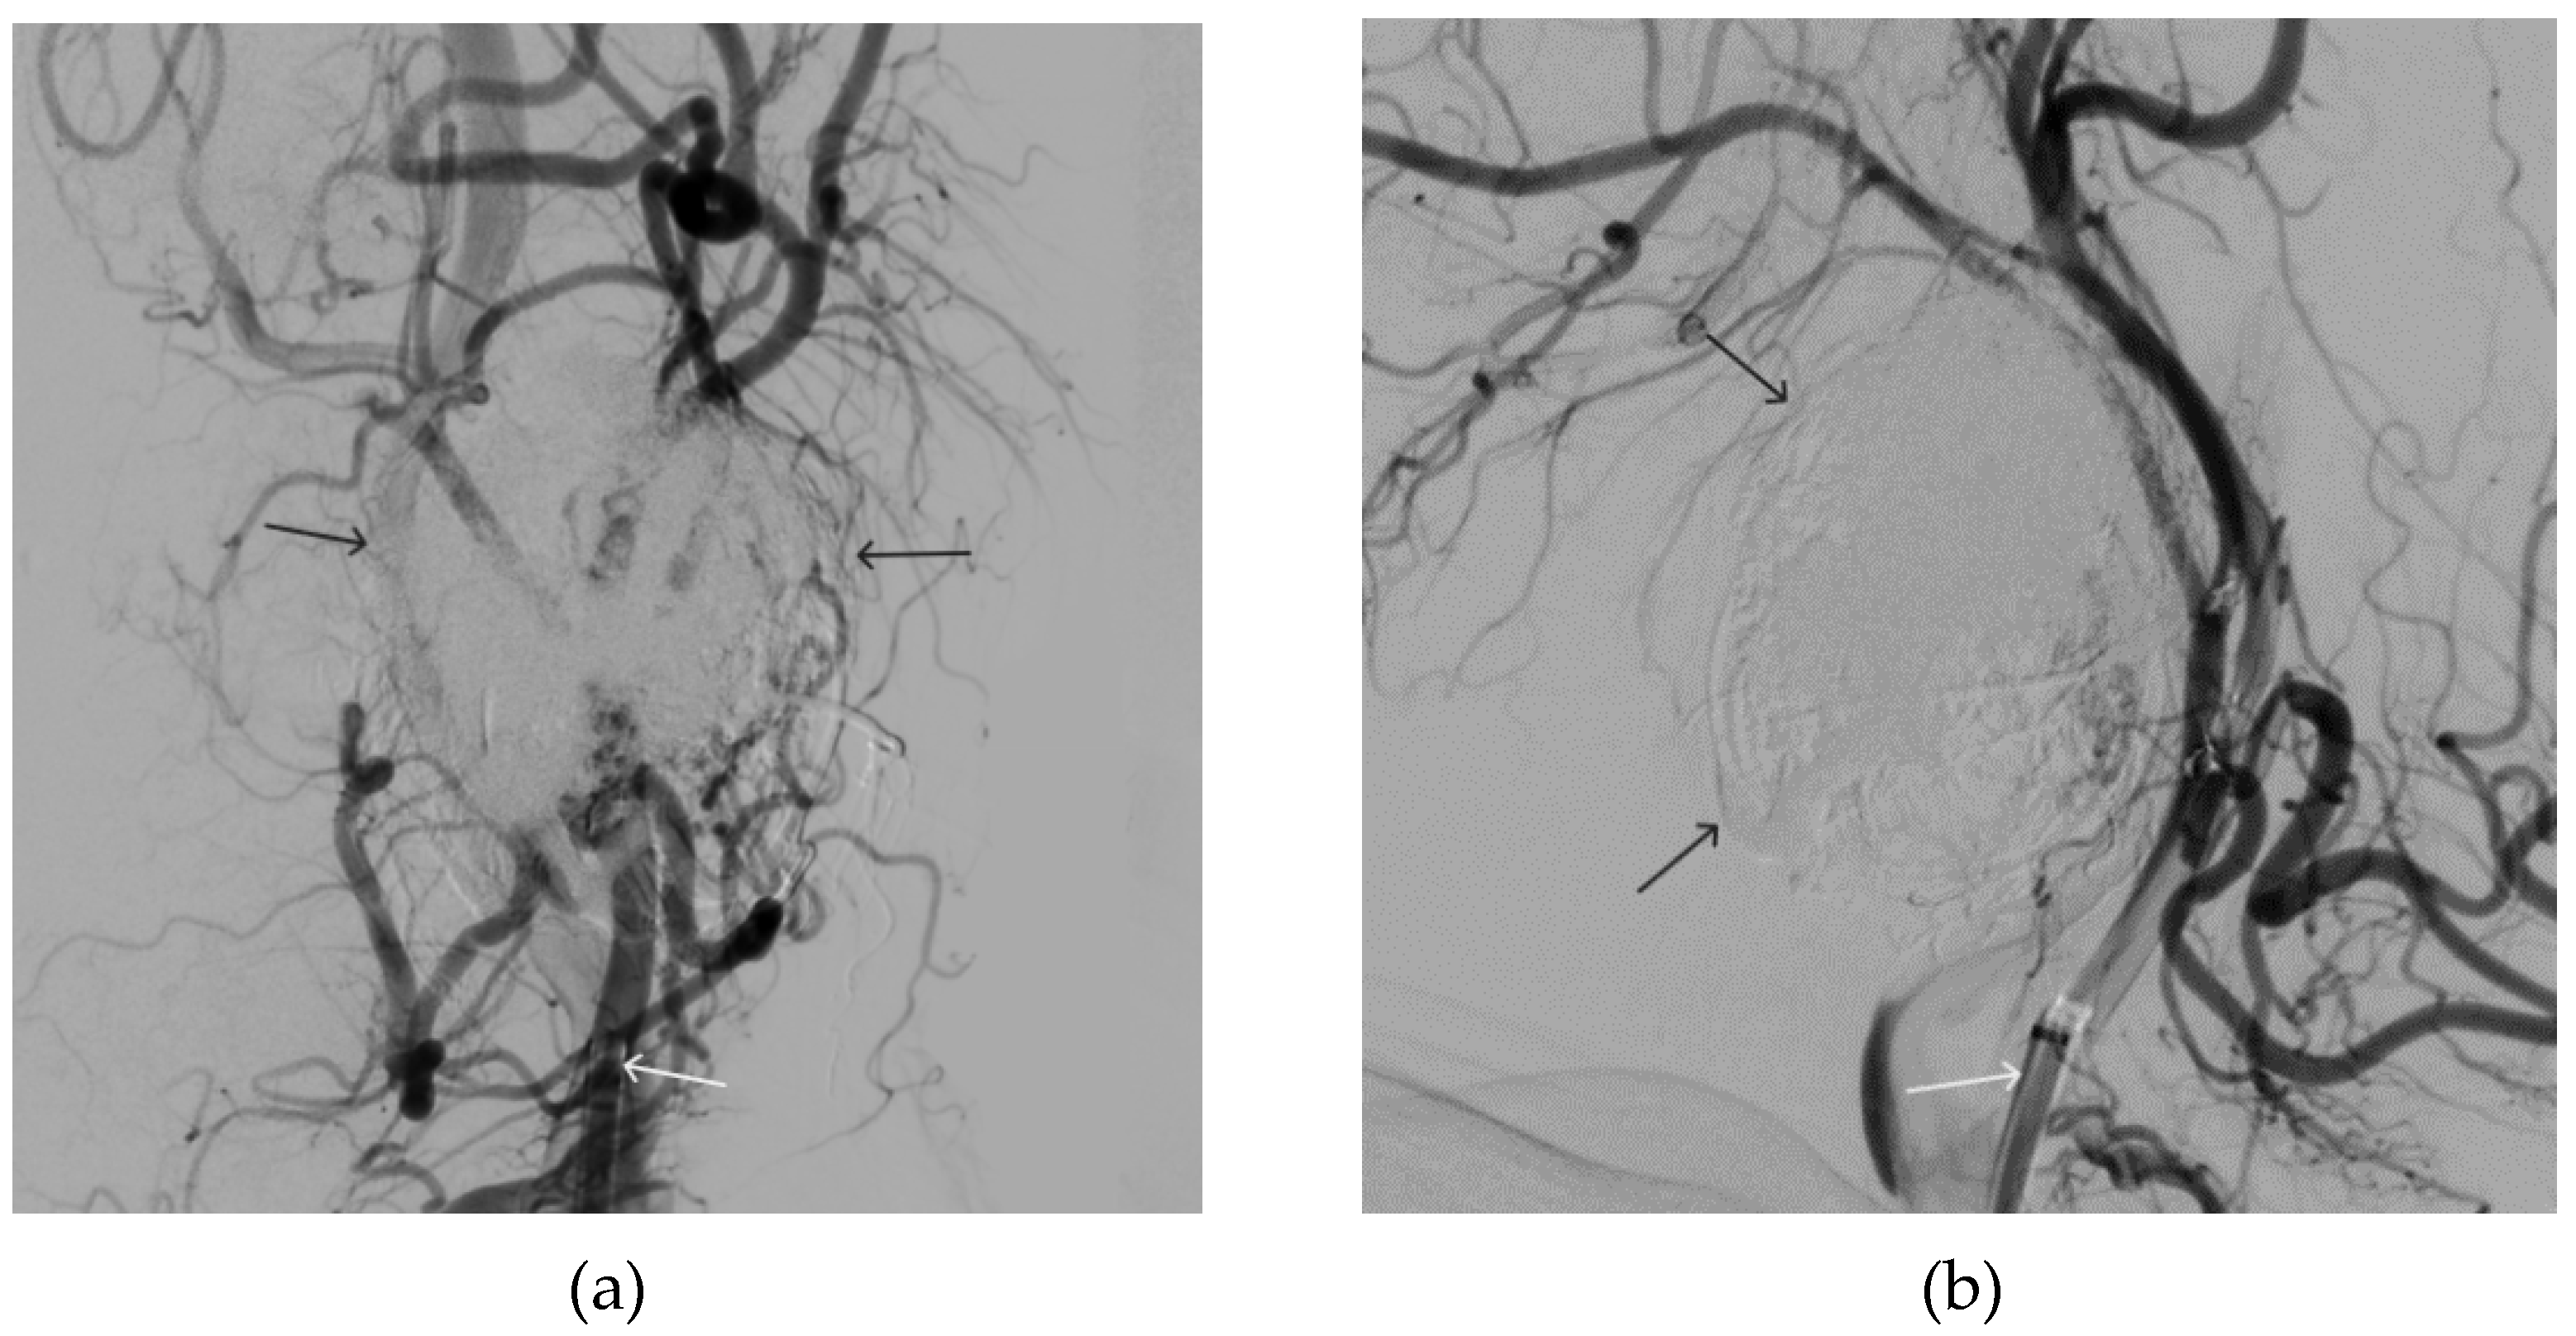

Figure 6. Digital subtraction angiography from the right and left facial arteries: a - direct projection; b - lateral projection (white arrows indicate catheters at the ostium of the facial arteries, black arrows indicate embolizate karst). The absence of AVM contrast is noted.